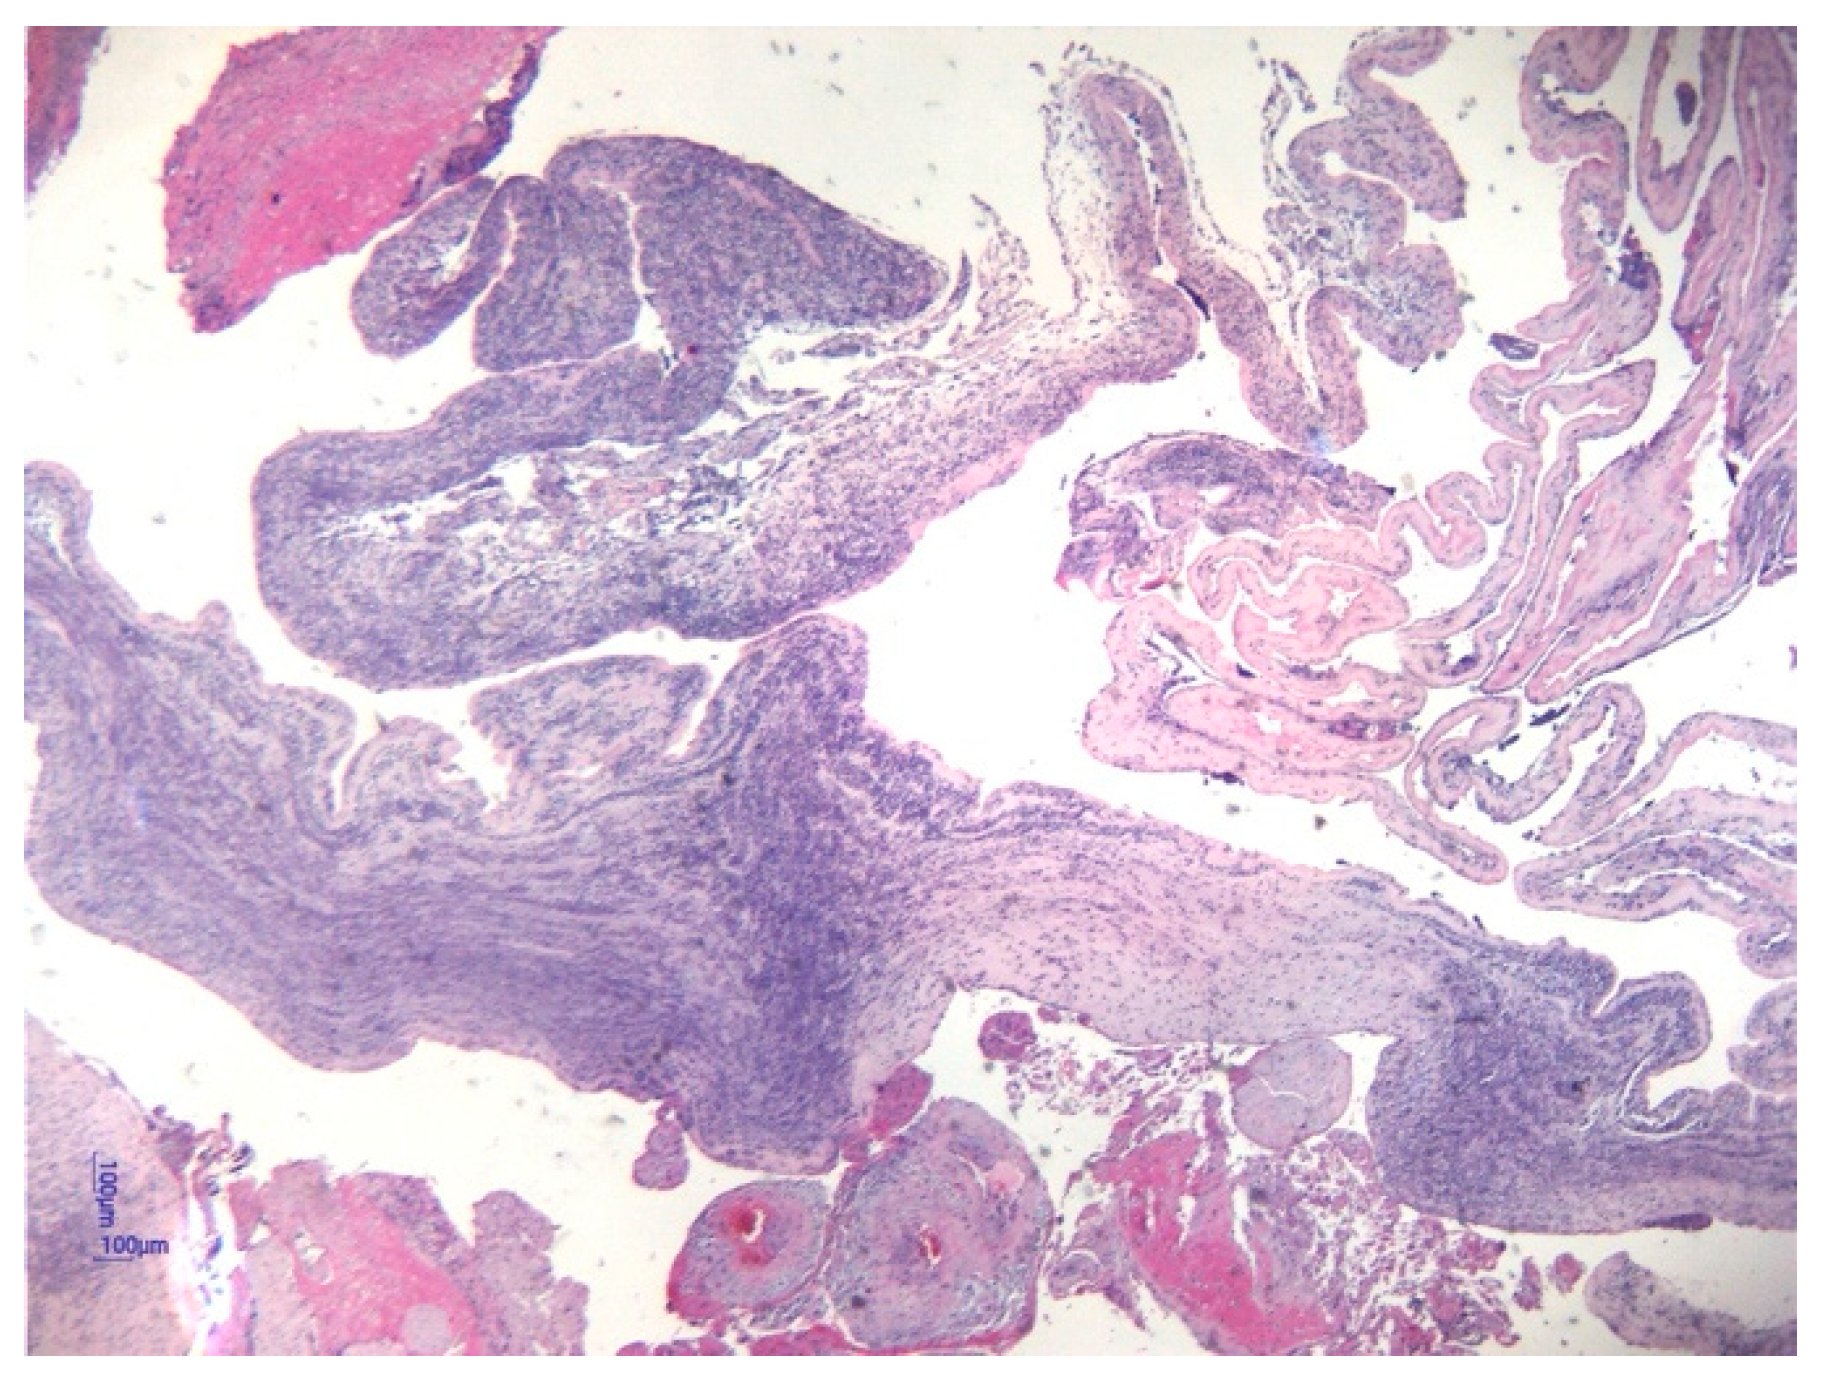

- Pacora, P.; Chaiworapongsa, T.; Maymon, E.; Kim, Y.M.; Gomez, R.; Yoon, B.H.; Ghezzi, F.; Berry, S.M.; Qureshi, F.; Jacques, S.M.; et al. Funisitis and chorionic vasculitis: The histological counterpart of the fetal inflammatory response syndrome. J. Matern. Neonatal Med. 2002, 11, 18–25. [Google Scholar] [CrossRef]

- Kim, C.J.; Romero, R.; Chaemsaithong, P.; Chaiyasit, N.; Yoon, B.H.; Kim, Y.M. Acute chorioamnionitis and funisitis: Definition, pathologic features, and clinical significance. Am. J. Obstet. Gynecol. 2015, 213 (Suppl. 4), S29–S52. [Google Scholar] [CrossRef] [PubMed]

| Corioamnionitis (n = 42) | 37 (88.1%) | 5 (11.9%) | 0.001 | |

| Funisitis (n = 37) | 33 (89.2%) | 4 (10.8%) | 0.001 | |